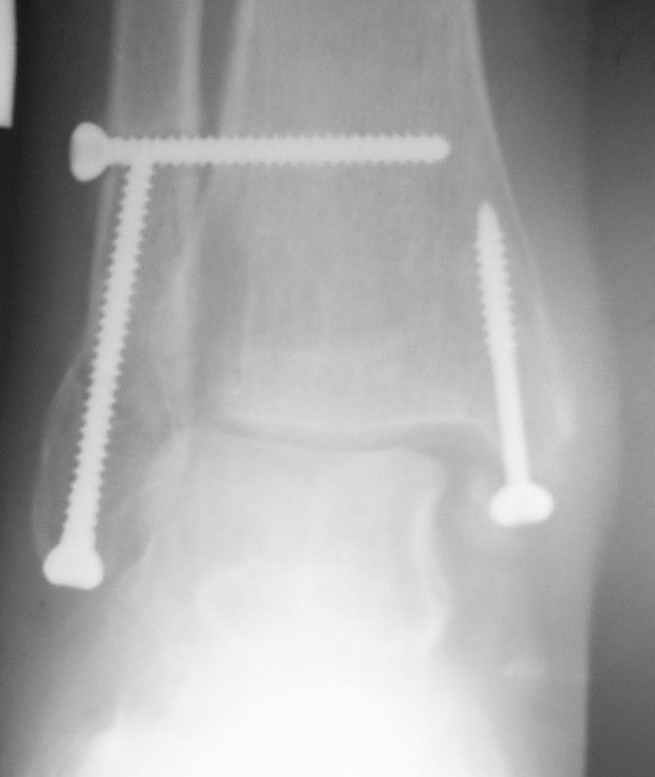

Ниже рентгенограммы

До операции 28 июля

Операция 29 июля

Через месяц

Боковой через месяц

15 ноября прямой

15 ноября боковой

15 ноября трехчетвертной

12 января прямой

12 января боковой

12 января трехчетвертной

Риторический вопрос - в каком руководстве рекомендован такой способ остеосинтеза наружной лодыжки?

Очевидно, такой результат операции был запрограммирован. При невосстановленной длине и практически нефиксированной малоберцовой кости (этот кортикальный винт - как карандаш в стакане), при неустраненном подвывихе, невправленной и тоже нефиксированной внутренней лодыжке нет стабильной вилки сустава. Если такую операцию сделать даже сразу, а не через 4 месяца, то результат ожидаем

тот же.

Вообще говоря, такое повреждение вполне успешно можно лечить без операции - если 6 недель подержать в гипсовом "сапожке" с хорошо устраненным подвывихом. Вероятное несращение внутренней лодыжки не обязательно компрометирует результат.

Если до сих ничего не сделано, с артродезом сустава в данный момент я бы повременил, на выставленных январских снимках хорошо сохранившийся сустав, а в "мортиз" (трехчетвертной) и на боковых снимках не менее 5 мм укорочение малоберцовой кости. Косые переломы лучше фиксировать пластинами, как то мы разбирали случай, где было отмечено, что это закон "таранная кость всегда следует за малоберцовой".